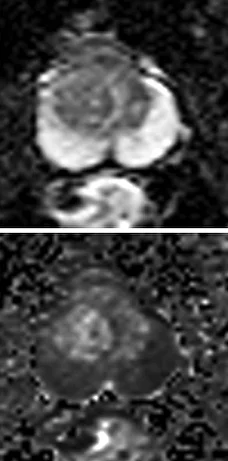

Transition Zone (TZ)

Неоднородная зона с нечеткими краями, все то, что не подходит в PIRADS 1-2 или 4-5

Вытянутой формы или не ограниченная гипоинтенсивная гомогенная зона, менее 1.5см

То же что и PIRADS 4, только размером более 1.5см или с распространением за пределы простаты

Ограничение диффузии: гипоинтенсивный на ADC и гиперинтенсивный на DWI.

Выраженное ограничение диффузии, очаг меньше 1.5 см